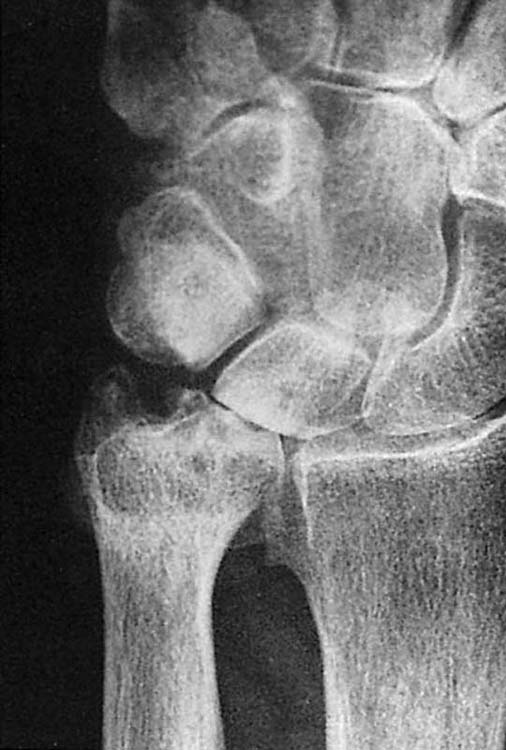

Bone density, which is evaluated grossly, may be normal, less than normal (osteopenia), or greater than normal (osteosclerosis). Osteopenia is most often encountered in the elderly and is known as senile osteoporosis when associated with advanced age. Osteosclerosis occurs in conditions such as avascular necrosis (AVN) (Fig. 13-2), fracture healing, and metabolic bone disease.2 Plain films may reveal discrete or diffuse bone lesions, including primary or metastatic bone tumors, infection, and metabolic bone disease (Fig. 13-3). The cortical integrity is carefully inspected for evidence of acute fracture (Fig. 13-4) and the joint alignment evaluated for subluxation or dislocation.3 Abnormalities of the articular surface and cartilage joint space also are documented. Narrowing of the cartilage space may indicate arthritis, resulting from degeneration, inflammation, infection, or trauma (Figs. 13-5 and 13-6).4 Finally, the soft tissue shadows are evaluated for irregularities. Any evidence of calcification (Fig. 13-7), foreign bodies (Fig. 13-8, online),5 or soft tissue masses must be correlated with the clinical findings.

images

Figure 13-2 Avascular necrosis (AVN) of the lunate, or Kienböck’s disease. Coned-down posteroanterior views of the wrist demonstrate two manifestations of AVN: bony sclerosis, seen in the ulnar aspect of the lunate, and osteopenia, seen in the radial side of the lunate (arrow). The latter is due to increased blood flow as the bone attempts to heal.

Figure 13-4 This posteroanterior view of the wrist shows a fracture of the proximal third of the scaphoid (arrow) with an associated cyst.